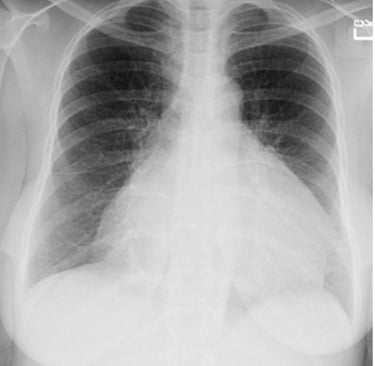

Chest X-ray was requested, and the patient was sent home while awaiting the results.

Question 2. What is the diagnosis ? Differential diagnosis?